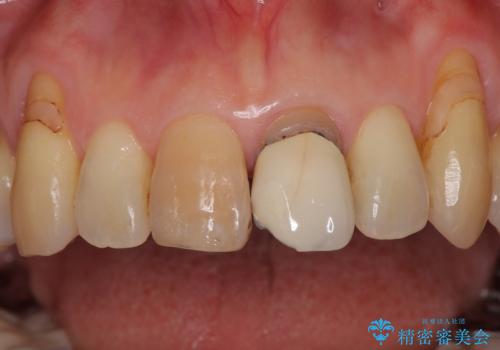

- 幼少期にぶつけてしまった前歯2本の変色を気にして来院された患者様です。

神経は生きているものの歯の色が茶色くなってきており、隣の歯は保険診療で装着したプラスチックのクラウンが徐々に黄ばんできている状態でした。

2本を同時にオールセラミッククラウンにて補綴治療を行うこととしました。